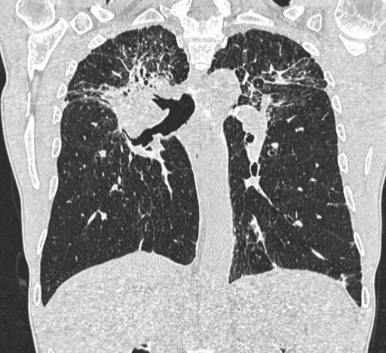

■ Cystic lesion (낭성 폐병변)

§ Cystic lung disease

- 공기를 포함한 투명한 공간 (air - containing lucency)

- 벽은 거의 식별할 수 없을 정도로 얇음 (thin wall)

- Diffuse cystic bronchiectasis

→ 세기관지의 확장으로 발생한 기관기 확장증

→ 폐상부 발생 : cystic fibrosis (낭포성 섬유증), Post TB

→ 폐중엽, 폐하엽 발생 : PCD(Primary ciliary dyskinesia_ 선천성 질환), 만성 감염증